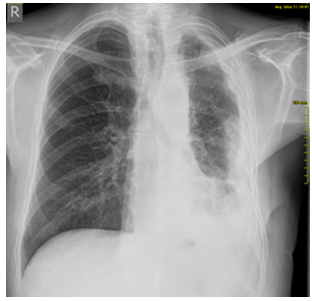

varijanta. Na kontrolnoj PA radiografiji grudnog koša od 16.09.2018.

godine (Slika 2) Leva hemidijafragma i levi KF sinus zasenjeni

senkom laterouzlaznog toka-prisutna pleuralna efuzija. Ostali deo

plućnog parenhima levo smanjene transparencije.

Slika 2. Kontrolna radiografija grudnog koša